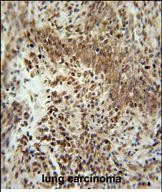

| IHC | 1/100-1/500 | Human,Mouse,Rat |